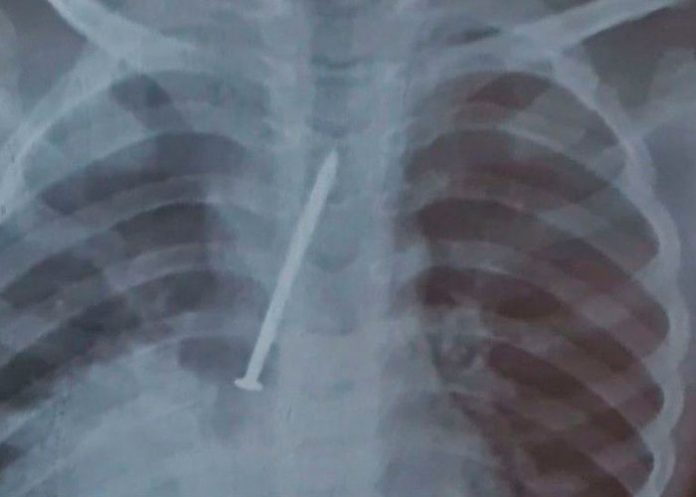

Los rayos x terminaron confirmando que había un objeto extraño en el cuerpo y decidieron operar. A pesar del esfuerzo ya el clavo había hecho daño en sus pulmones.

En el Hospital General del Estado (HGE), el nene fue operado para quitarle el clavo de sus pulmones. Los galenos descubrieron que el material había perforado ambos pulmones del pequeño, quien estuvo días hospitalizado en la Unidad de Cuidados Intensivos (UCI) antes de fallecer.